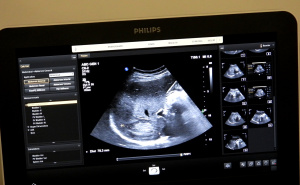

U edukacionom centru Kantonalne bolnice Zenica uspješno je okončan drugi napredni kurs ultrazvuka abdomena u Zeničko-dobojskom kantonu (ZDK), čime je zaokružen ciklus kontinuirane edukacije ljekara započet prošle godine ranijim bazičnim kursevima i preventivnim aktivnostima.

Završetkom ovog kursa još devet ljekara, odnosno ukupno 18 ljekara steklo je certifikate za samostalan rad u ultrazvučnoj dijagnostici abdomena, što predstavlja značajan iskorak u povećanju dostupnosti dijagnostičkih pregleda i jačanju preventivne zdravstvene zaštite u lokalnim zajednicama.

"Okončali smo dva ciklusa koji su se sastojali u kontinuiranoj edukaciji od bazičnog i naprednog kursa. Sa današnjim danom su izeducirano 18 ljekara koji mogu da obavljaju samostalno ultrazvučne preglede abdomena, što je nama jako drago, jer to će biti najveći benefit pacijenata. Grupa kolega koje su završili prethodni napredni kurs rade već samostalno. Tako da će i kolege koji su danas završili kurs, nadam se, ubrzo početi samostalni rad", ističe dr. spec. radiologinja Aida Vehabović, koja je predvodila tim edukatora, u kojem su bili i dr. Lejla Šaranović Čečo i dr. Alen Okanović.

Ovaj intenzivni edukativni program je obuhvatio 750 pregleda pacijenata, od čega 400 preventivnih, te 350 pregleda ostalih pacijenata koji su bili upućivani pretežno iz Doma zdravlja sa određenim uputnim dijagnozama i različitim patologijama, uključujući onkološke, endokrinološke, hematološke, nefrološke, te razni internistički slučajeve, koji su imali i problematiku abdomena

Edukacijom se stvara veći broj educiranih doktora koji mogu samostalno i sigurno raditi ultrazvučne preglede, što direktno povećava dostupnost dijagnostičkih pretraga pacijentima. Što više obučenih ljekara imamo, to su liste čekanja kraće, a građani brže dolaze do pregleda, posebno kada je riječ o preventivnim kontrolama. Organizatori su zahvalili kompaniji Farmavita na podršci realizaciji edukacije, kao i Philipsu, koji je ustupio dodatne uređaje za edukaciju.